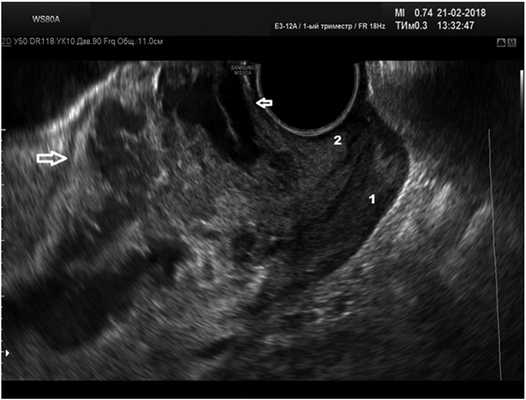

У 3 (15,8%) пациенток при первичном обращении в сроки беременности 10 нед (1 беременная) и 13 нед (2 пациентки) при неразвивающейся беременности отмечены признаки врастания хориона с тотальной деструкцией нижней трети передней стенки матки, перешейка и частично верхней трети передней губы шейки матки с признаками инвазии хориона в стенку мочевого пузыря (рис. 4). Попытки метропластики в данной ситуации интраоперационно осложнились кровотечением, по жизненным показаниям объем операции расширен до гистерэктомии.

Рис. 4.Тотальная деструкция передней стенки матки в области рубца, частичная деструкция передней губы шейки матки при беременности в рубце.

1 — задняя губа шейки матки; 2 — передняя губа шейки матки; между стрелками — зона деструкции.